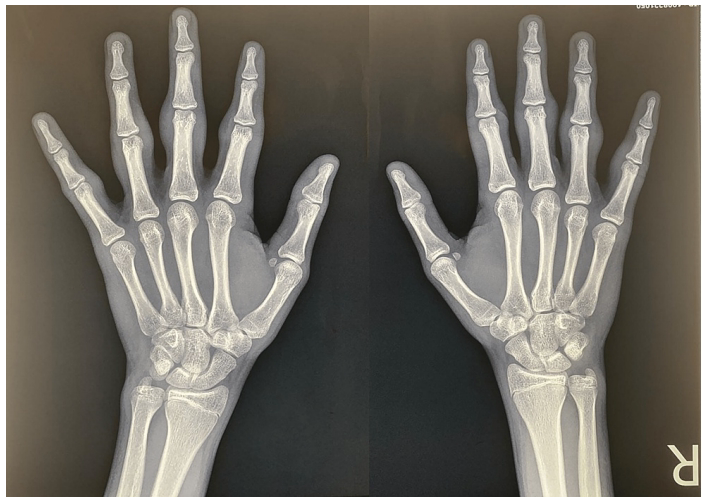

影像学特点:

鉴别诊断的关键武器

影像学检查在厚皮指症诊断中的核心价值在于“排除”和“证实”——排除炎性关节炎,证实良性软组织增生。

X线平片:仅显示关节旁软组织影增厚,呈梭形。

· 关键阴性发现:无关节间隙狭窄、无骨侵蚀、无骨膜反应、无